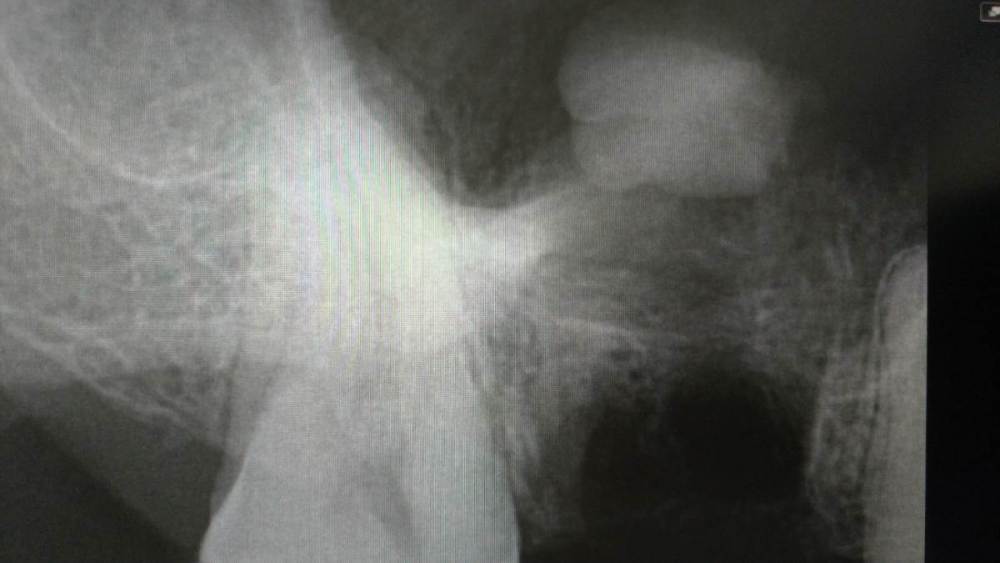

HAV Опубликовано 3 апреля, 2021 Поделиться Опубликовано 3 апреля, 2021 Всем здравствуйте. При удалении 1.6 зуба медиальный щечный корень продвинут в пазуху. Достать корень в это же посещение не удалось, наложены швы. Подскажите пожалуйста, кака тактика должна быть в такой ситуации? Слышал, что коллеги достают такие корни используя слюноотсос, маршевый тампон и т.д... Правильно ли я представляю себе, что для этого необходимо создать соустье достаточной ширины, чтобы в пазуху проходила трубка слюноотсос, и после извлечения корня из пазухи закрывать это соустье проводя пластику мягкими тканями? Каковы шансы достать корень при такой тактике? И как правильно, извлекать корень в удаления зуба, или отсрочено, вторым этапом? Хотелось бы услышать мнение опытных коллег. Спасибо. Ссылка на комментарий

DShu Опубликовано 10 апреля, 2021 Поделиться Опубликовано 10 апреля, 2021 Во-первых, необходимо убедиться, что корень в пазухе, не под слизистой. Если второй вариант (а такое бывает), то к ЛОРу точно смысла нет направлять. Если есть КТ в клинике, то проще достать самому, через переднюю стенку, как при ОСЛ. С одномоментной пластикой соустья. Но это можно делать в первые 48 часов после удаления. Либо уже через 2 недели. к ЛОРу отправить - самый простой вариант. Но есть шанс, что придётся заплатить за FESS из своего кармана. Достать марлей, отсосом - примерно такие же шансы, как высморкать его. Иногда и такое получается. Удачи! 2 1 Ссылка на комментарий